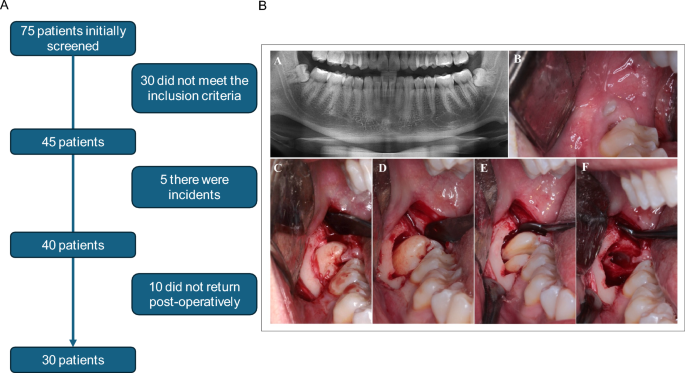

The study initiated with an interview and evaluation of 75 patients. Of these, 30 did not meet the inclusion criteria. Of the remaining 45, five presented complications during or after the surgery, such as bleeding, infections and failure in tooth extraction, totaling 40 operated patients. Given that another 10 did not return for the postoperative follow-up, in total 30 patients were included in the study (Fig. 1A).

A- Flowchart of the individuals selected according to CONSORT guidelines. Initially, 75 patients were screened; of these, 30 did not meet the inclusion criteria, resulting in 45 eligible patients. Among them, 5 experienced postoperative complications and were excluded, totaling 40 patients who underwent the surgical procedure. Of these, 10 did not attend the postoperative follow-up, thus 30 patients were included in the final analysis. B-Illustrative sequence of the standardized surgical procedure performed for the removal of impacted mandibular third molars. The images represent: (A) panoramic radiograph showing a patient eligible for the study; (B) initial clinical view of the surgical site; (C) exposure of the anatomical structure of interest; (D) performance of the osteotomy; and (E) tooth sectioning (odontosection). All procedures were carried out by a trained surgical team, following a standardized protocol to ensure consistency and reproducibility across cases.

A linear triangular mucoperiosteal incision was made with a number 15 scalpel blade in the distal region of the 2nd lower molar, associated with a vestibular relaxing incision in the mesial region of the 2nd molar. Subsequently, mucoperiosteal detachment was performed. The osteotomy was performed using a truncated conical carbide bur n. 702 mounted on a handpiece. Tooth removal was completed with curved and straight extractors, followed by a careful inspection to remove the pericoronal follicle. The bone edges were filed to remove the bone spicules with a bone file, whereafter abundant irrigation was performed with sterile 0.9% NaCl saline solution. After this surgical step, interrupted sutures were put in place using 5.0 nylon thread. The surgeries were performed in the morning (between 8 and 10 am), so that there would be no interference from diurnal variations in cortisol levels2,3 (Fig. 1B).